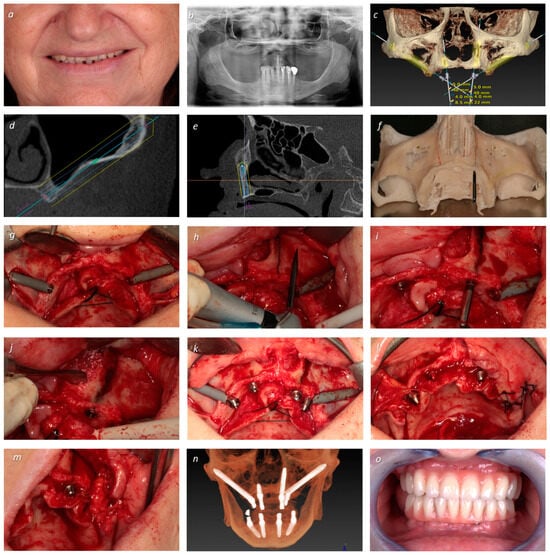

| 3 | EM 0° 5 × 40 | S 4 × 10 | T 3.75 × 22.5 | EM 0° 5 × 40 | 64 | F | 3 | I | NG | +50 |